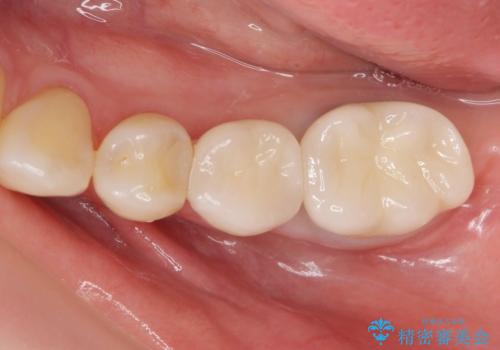

- 銀歯のやりかえ希望の患者様です。

症状もなく、レントゲンでも根尖病巣が見られないため

患者様と話し合った結果、中の土台は外さず、被せ物のみのやりかえとなりました。

- ジルコニアクラウン・仮歯 12.1万円費用は治療当時の料金となります